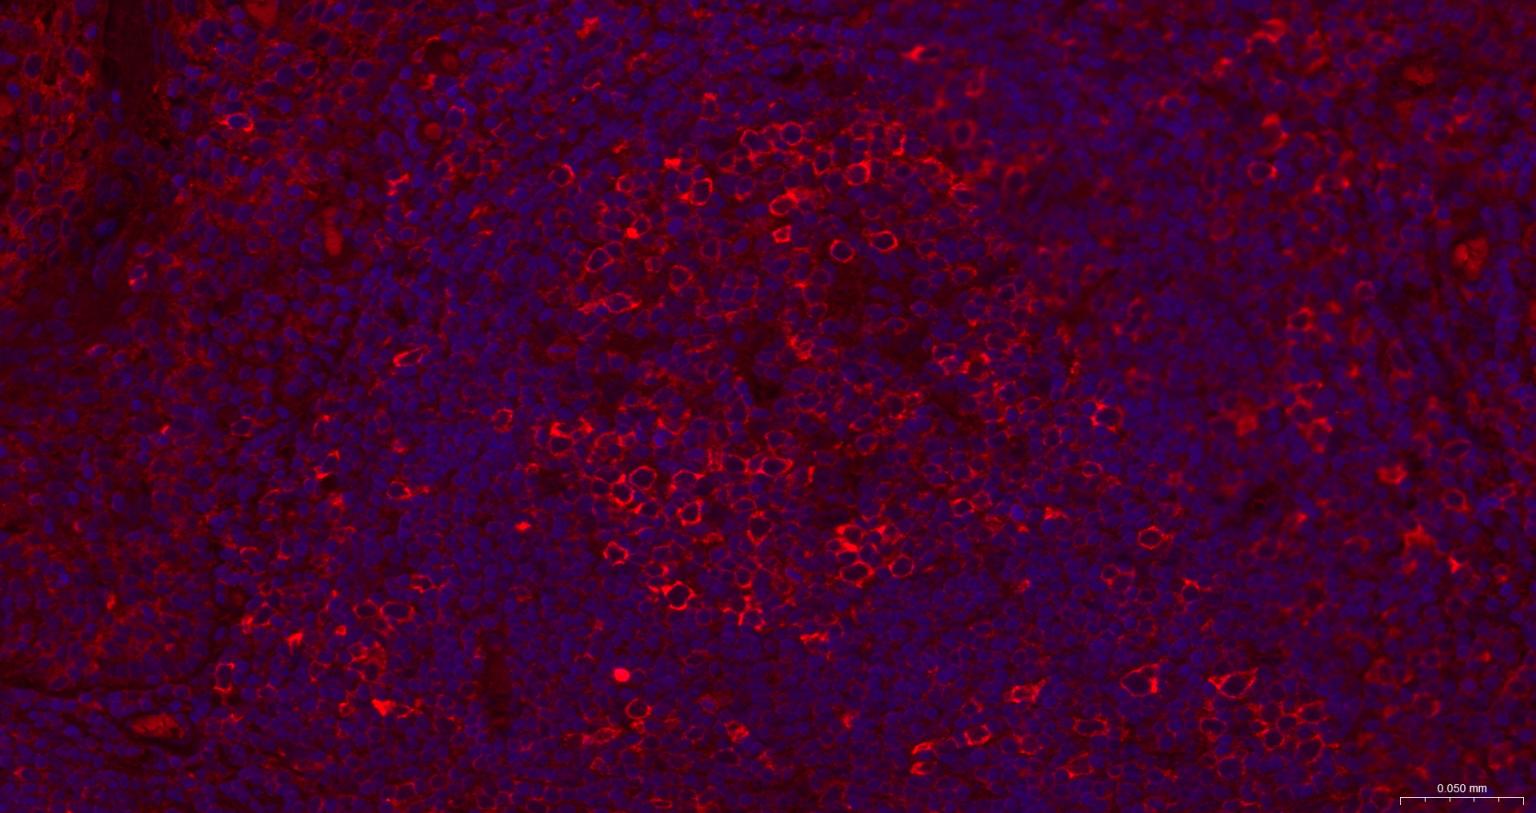

Paraformaldehyde-fixed, paraffin embedded Human Tonsil; Antigen retrieval by boiling in sodium citrate buffer (pH6.0) for 15 min; The section was incubated with GART Monoclonal Antibody, Unconjugated (bsm-52537R) at 1:200 overnight at 4°C. Followed by conjugated Goat Anti-Rabbit IgG antibody (Red, bs-0295G-BF594), DAPI (blue, C02-04002) was used to stain the cell nuclei.

Paraformaldehyde-fixed, paraffin embedded Human Colon Cancer; Antigen retrieval by boiling in sodium citrate buffer (pH6.0) for 15 min; The section was incubated with GART Monoclonal Antibody, Unconjugated (bsm-52537R) at 1:200 overnight at 4°C. Followed by conjugated Goat Anti-Rabbit IgG antibody (Red, bs-0295G-BF594), DAPI (blue, C02-04002) was used to stain the cell nuclei.